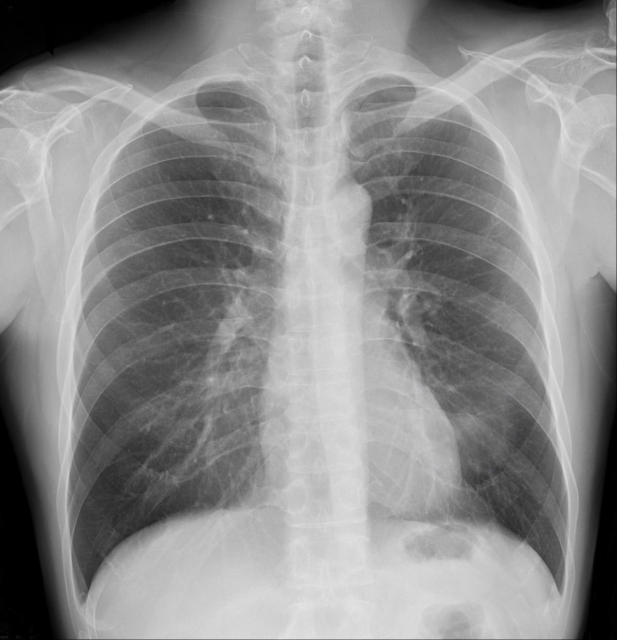

「最近ちょっと息切れしやすいな」「咳が長く続いているな」と感じることはありませんか?呼吸にまつわる不調は、年齢や体力のせいだと思ってしまいがちですが、実は肺の健康状態が関わっていることもあります。そんなときに役立つのが、呼吸の状態を数値で確認できる「肺機能検査」です。

肺機能検査は、息を吸ったり吐いたりする力や量を測定することで、肺の健康状態を評価します。基本となる項目は「肺活量」と「努力性肺活量」です。肺活量とは、深呼吸をして吸い込んだ空気をゆっくりと吐き出したときの量を指します。肺の容量そのものを確認できるため、健康な肺の基準値と比較することで、肺が十分に働いているかどうかを判断できます。

一方、努力性肺活量は、吸い込んだ空気を一気に勢いよく吐き出して測定します。息を吐きだす速さや量を調べることで気道が狭くなっていないか、空気の通り道に障害がないかを評価します。特に、喘息や慢性閉塞性肺疾患(COPD)などの早期発見に有用で、喫煙歴がある方にとっては大切な検査です。